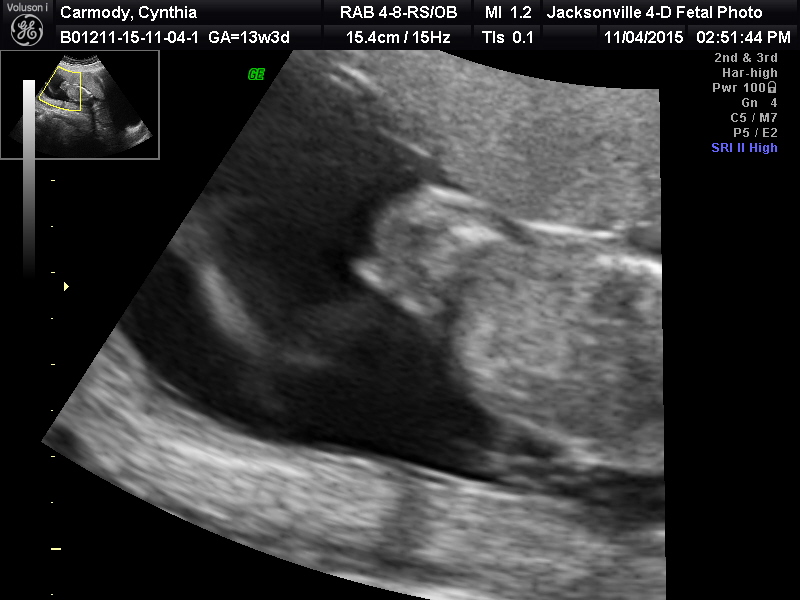

Attachment 28265Attachment 28261Attachment 28262Attachment 28263Attachment 28232Attachment 28232

I know I accidentally posted this in the wrong section. First time using this site, I didn't know how to delete it. But can you tell the gender with the pics posted?